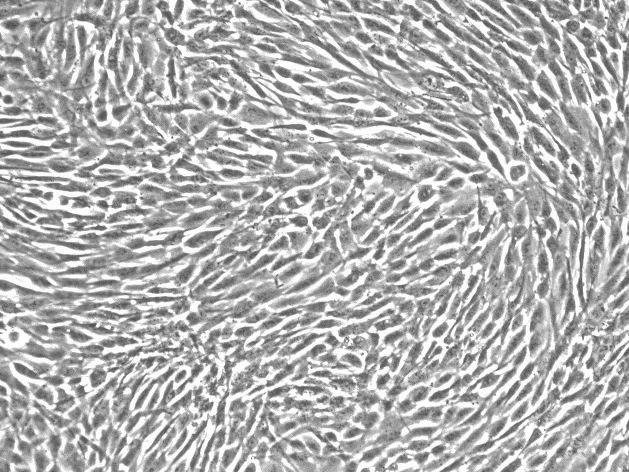

生长特性:贴壁细胞

背景描述:TE-11(人食管癌细胞)详询